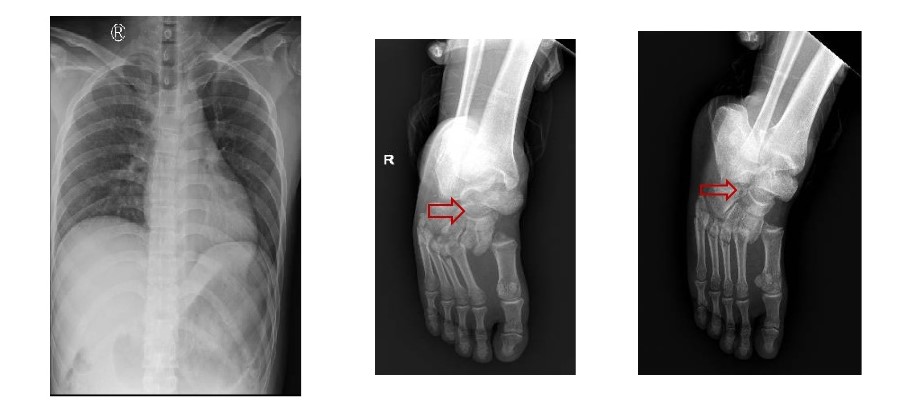

Kết quả chụp Xquang ngực thẳng, cổ bàn chân phải của các bệnh nhân. (Ảnh: Bệnh viện cung cấp)

2 bệnh nhân nam nhập viện trong tình trạng đau đớn, liệt hoàn toàn 2 chân, bí tiểu… Khai thác bệnh sử, trong lúc nam bệnh nhân 28 tuổi, quê ở Hải Dương, đang sửa cáp thang máy thì người đồng nghiệp (26 tuổi, quê Tiền Giang) bước vào thang khiến thang quá tải rơi xuống từ lầu 7.